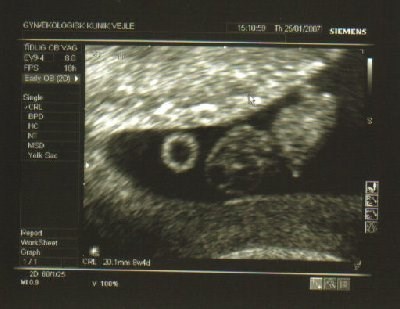

- jeg er 8+3..